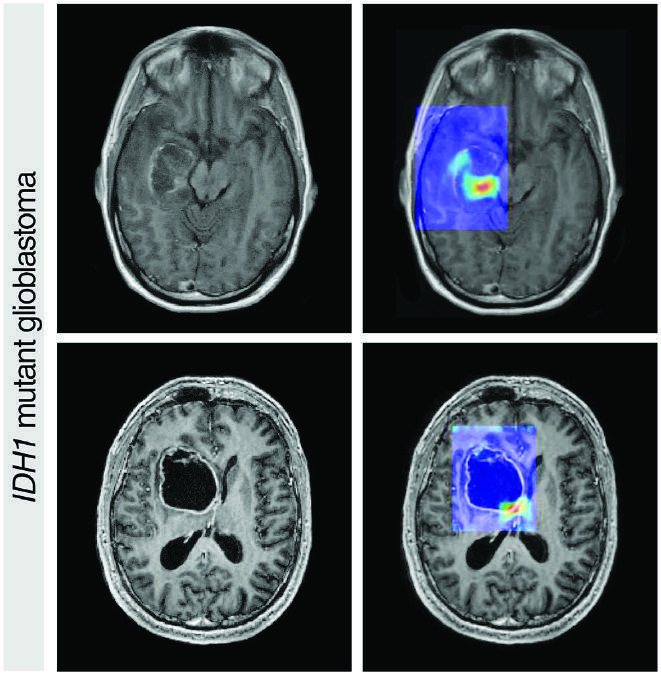

AI chua ung thu anh 5

Một thuật toán học sâu được huấn luyện để phân tích hình ảnh từ các lần quét MRI dự đoán sự hiện diện đột biến gen IDH1 trong các khối u não. Ảnh: CA Cancer.